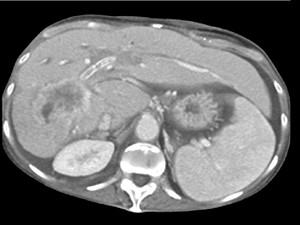

问题 男,50岁,右上腹痛,进行性黄疸,无腹部包块,AFP阴性,影像检查如图,最可能的诊断是 ( )

选项 A、肝腺瘤 B、肝转移瘤 C、胆管癌 D、肝血管瘤 E、肝细胞肝癌

答案 C